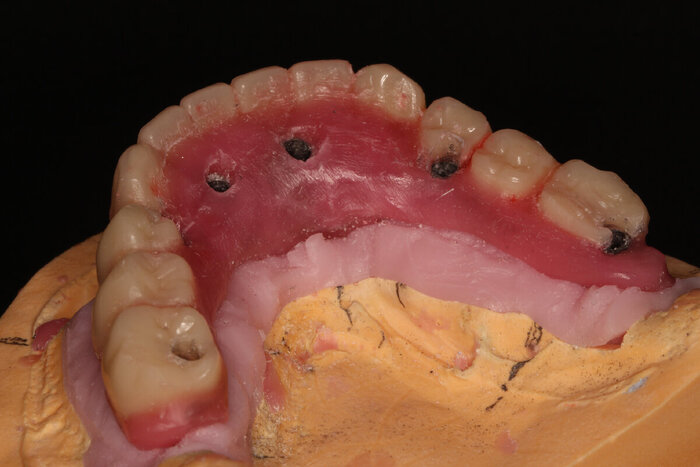

Я уже писала о распечатанном прототипе, точно повторяющем верхнюю челюсть пациента - вот, теперь показываю его вам.

Посмотрим на восковой протез нижней челюсти поближе.

Примеряем в полости рта. Посмотрим, даст мне робот за зубы человека на пряники или пощадит.

Теперь наносим фиолетовую коррекцию, что бы техники оценили весь масштаб поправок.